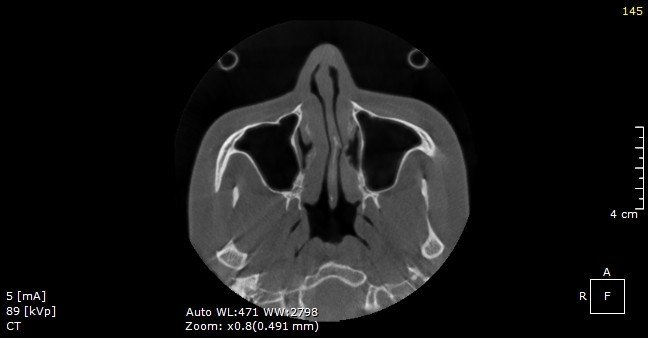

BS.CKI Nguyễn Hoàng Nam - Giám đốc chuyên môn Phòng khám AZ Nose - cho biết chụp CT 3D giúp khảo sát cấu trúc mũi của khách hàng, bao gồm tình trạng vách ngăn, xương mũi, da, xoang mũi, cuốn mũi... Đây là phương pháp giúp bác sĩ xác định được nguyên nhân mũi hỏng và đưa ra giải pháp phù hợp.

“Phần lớn mũi khách hàng bị lệch, vẹo sau nâng là do bác sĩ trước đó không xử lý được tình trạng lệch vách ngăn, xương bè và xương gồ mũi khiến phần sống bị lệch khỏi vị trí cố định ban đầu. Ngoài ra, phần sụn nhân tạo không được cố định chắc chắn, trụ mũi dựng không vững hoặc mũi bị va đập mạnh cũng là nguyên nhân dẫn đến tình trạng này. Do đó, việc hiểu về cấu trúc và tình trạng mũi thực tế của khách hàng giúp bác sĩ có thể đưa ra giải pháp khắc phục tối ưu nhất, đảm bảo hiệu quả thẩm mỹ cao”, bác sĩ Hoàng Nam cho biết.

Vách ngăn lệch trái sâu của một khách hàng trên hình chụp CT 3D.